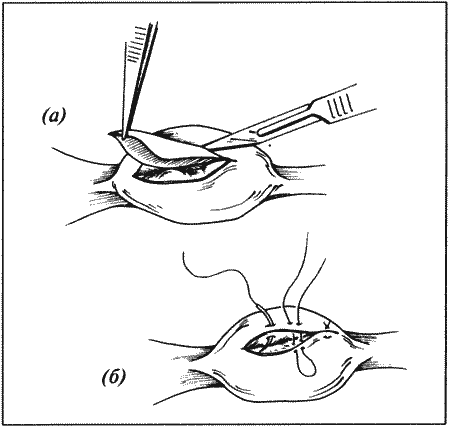

Рассматриваются следующие вопросы: нормальная физиология собак и кошек; болезни репродуктивной системы; бесплодие самок и бесплодие самцов; нормальное функционирование и дисфункция молочных желез; спаривание; искусственное осеменение; протекание беременности и роды; уход за новорожденными щенками и котятами, их наследственные и инфекционные болезни; техника оперативных вмешательств на репродуктивных органах; фармакологический контроль репродукции.

В Руководстве приводится обзор нормальной физиологии и эндокринологии размножения собак и кошек, рассматриваются причины бесплодия самок, функция и дисфункция молочных желез, нарушения, возникающие у небеременных самок, а затем столь же подробно описываются соответствующие проблемы у самцов. Далее обсуждаются вопросы спаривания и искусственного осеменения, а также протекание беременности и родов. Специальный раздел посвящен наблюдению и лечению новорожденных щенков и котят; он включает обзорные данные по наследственным порокам, обсуждение роли инфекционных болезней и мер по их предупреждению. В заключительных главах книги рассматриваются терапевтические и хирургические методы, применяемые для коррекции репродуктивных нарушений.